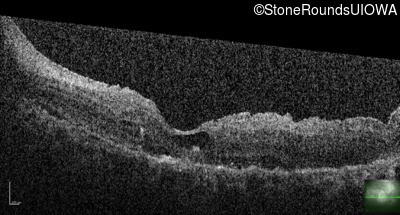

Optical Coherence Tomography - Right - 20/50 +2

Exemplar / OCT Stack